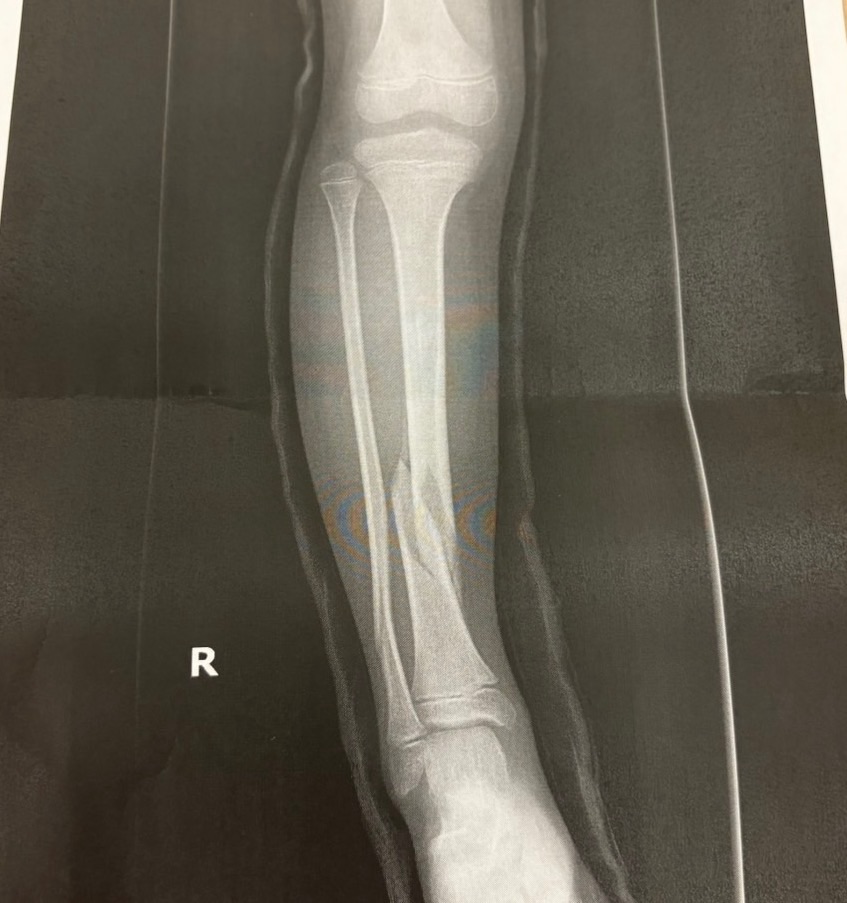

4月に脛骨2箇所、腓骨1箇所を骨折しまして…

怪我がかなり重症の部類でしたので、